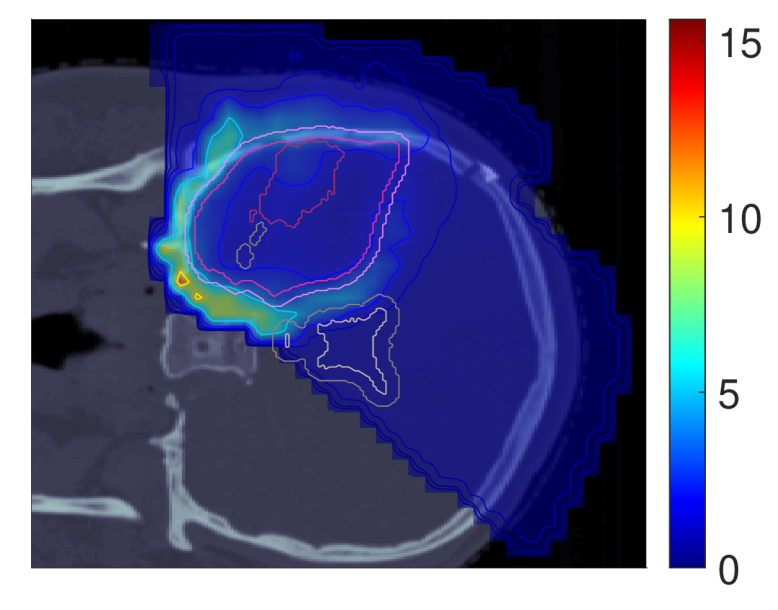

Figure 2 shows the optimal slice images of the dose (left), dose-averaged LET (middle) and POLO distribution (right). On the underlying CT scan, the tumor volumes are marked by violet to purple contours, while the VS (ventricles and 4 mm4\text{\,}\mathrm{mm} fringe) is outlined in white and gray. We observe the high-dose region covering all of the GTV, with a largely homogeneous transition to the clinical and planning target volumes (CTV, PTV), and a moderate to severe overlap to the VS. The dose-averaged LET distributes in layers, with increased values around the contour edge of CTV/PTV and local peaks at the distal ends of the proton beams. Accordingly, hot spots on the POLO map are found in regions where dose and dose-averaged LET scale up, or close to the VS. Beyond the PTV, the POLO map reveals cold spots, due to the steepness of the dose and dose-averaged LET gradients.

dRBE,fxd_{RBE,fx}ABCD ldl_{d}ABCD ppABCD

Refer to caption Refer to caption Refer to caption

NTCP:45.59 %NTCP:$45.59\text{\,}\mathrm{\char 37\relax}$ABCD

Figure 2: Optimal 2D slice images of the RBE-weighted fractional dose dRBE,fxd_{RBE,fx}, the dose-averaged linear energy transfer ldl_{d} and the probability function values pip_{i} for the baseline plan. The dose distribution (left) shows high target coverage with decreasing exposure beyond the CTV/PTV margins, but also visibly overlaps with parts of the VS. Meanwhile, for the dose-averaged LET (middle), layered homogeneity in the target volumes and local maxima at the distal ends of the proton beams can be observed. This results in more pronounced levels of POLO values within the target volumes, particularly in the presence of local dose-averaged LET maxima and in the environment of the VS. Referring back to the POLO model from Equation 1 and (3), we can expect exactly this type of coherence between the model output, the physical input feature profiles and the increased local risk near the VS. The baseline treatment plan exhibits a complication risk of 45.59 %45.59\text{\,}\mathrm{\char 37\relax} after evaluation of the POLO distribution with NTCPpNTCP_{p}.